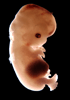

Carnegie Stage 22 (54 post-ovulatory days)

Most embryos at stage 22 are approximately 54 postovulatory days old and measure 25-27 mm in length. Distinguishing criteria for this stage include clear formation of the external ear, the hands begin to extend ventrally beyond the body wall, the fingers of one hand may overlap the fingers of the opposite hand, thickened eyelids just begin to cover the outer margins of the eye, and the superficial vascular plexus of the head now extends about three-quarters of the way above the eye-ear level.